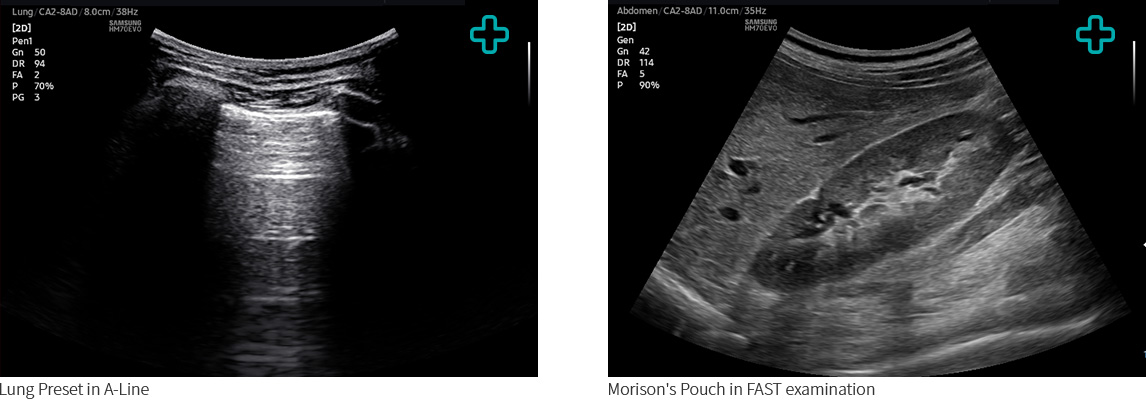

The HM70 EVO supports a wide range of clinical applications, environments, and patient types—including abdomen, cardiac, vascular, musculoskeletal, breast, emergency, and small parts. Especially, HM70 EVO reinforces the EM application with Lung and FAST presets. The versatility enables healthcare professionals to perform effectively on targeted examinations.

Lung Preset in A-Line, Morison's Pouch in FAST examination Lung Preset in A-Line, Morison's Pouch in FAST examination